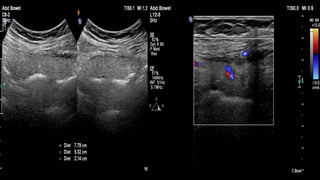

This document discusses the evaluation of right lower abdominal pain and lists appendicitis as a key cause. It notes that other potential causes include hemorrhagic cysts, heterotrophic pregnancy, salpingitis with pyosalpinx, funiculitis, and torsion of an undescended testis. The document was presented by Dr. A.S.M. Sufian of Cumilla Medical College Hospital and thanks the audience for their patience and listening.